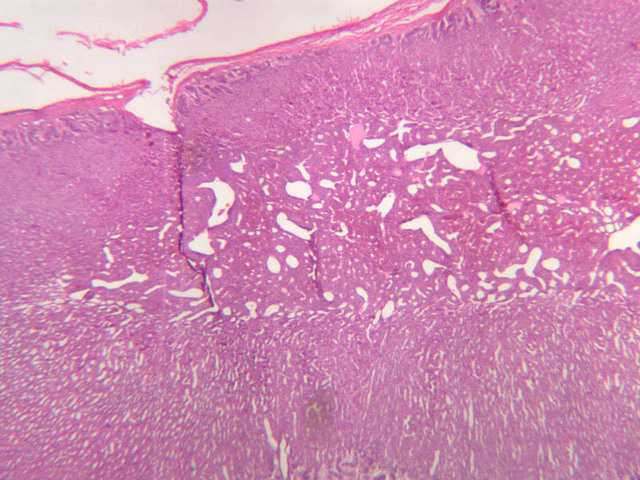

The adrenal gland (slide B-59, H&E [2.5x-labeled, 10x-labeled, 20x, 40x-labeled] [2.5x, 10x-labeled, 20x, 40x]; B-60, H&E [2.5x-labeled, 10x, 20x, 40x]; B-62, H&E [10x, 20x, 40x] [2.5x, 10x]) is a composite organ consisting of two functionally, structurally and embryologically different parts—an outer cortex and an inner medulla. Observe the gland at low power. Find the loosely organized tissue that comprises the medulla and the partially-separated columns of cells that make up the cortex. Scan the capsule and the tissue around it, looking for nerves and blood vessels. Study the pattern of cortical vasculature. In a pattern similar to that seen in the pars distalis of the pituitary, sinusoids run along the edges of columns or cords of cells. Owing to different arrangements of its constituent cells, the adrenal cortex has a layered appearance. From the capsule inward, these cortical layers are known as the zona glomerulosa, the zona fasciculata, and the zona reticularis.

The zona glomerulosa is located immediately beneath the capsule (B-60 adrenal gland, dog [10x, 20x] [20x, 40x]; B-59 [2.5x, 10x, 20x] [2.5x, 10x, 20x]). Its constituent cells are arranged in arcs or spheres, and, owing to their relatively small size, their nuclei appear to be close together. Cells of the zona glomerulosa secrete mineralocorticoids (e.g., aldosterone). The zona fasciculata consists of parallel columns or cords of cells that radiate toward the medulla and are separated by blood sinusoids (B-60 [2.5x, 10x, 20x, 40x]; B-62 [20x, 40x]). Owing to the extraction of lipids during histological processing, the cytoplasm of cells in the zona fasciculata appears highly vacuolated or "foamy". Cells of the zona fasciculata secrete glucocorticoids (e.g., hydrocortisone & cortisone) and some gonadocorticoids (weak androgens). The zona reticularis is the deepest cortical layer and lies adjacent to the medulla (B-60 [20x, 40x]; B-62 [20x, 40x]). It is characterized by irregular, interconnecting cords of cells which are separated by anastomosing capillary networks or sinusoids. Cells of the zona reticularis, which are smaller than those of zona fasciculata and do not contain as many lipid vacuoles, secrete gonadocorticoids and some glucocorticoids.